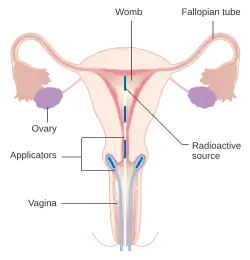

Early stages (IB1 and IIA less than 4 cm) can be treated with radical hysterectomy with removal of the lymph nodes or radiation therapy. Radiation therapy is given as external beam radiotherapy to the pelvis and brachytherapy (internal radiation). Women treated with surgery who have high-risk features found on pathologic examination are given radiation therapy with or without chemotherapy to reduce the risk of relapse. A Cochrane review has found moderate-certainty evidence that radiation decreases the risk of disease progression in people with stage IB cervical cancer when compared to no further treatment.[113] However, little evidence was found on its effects on overall survival.[113]